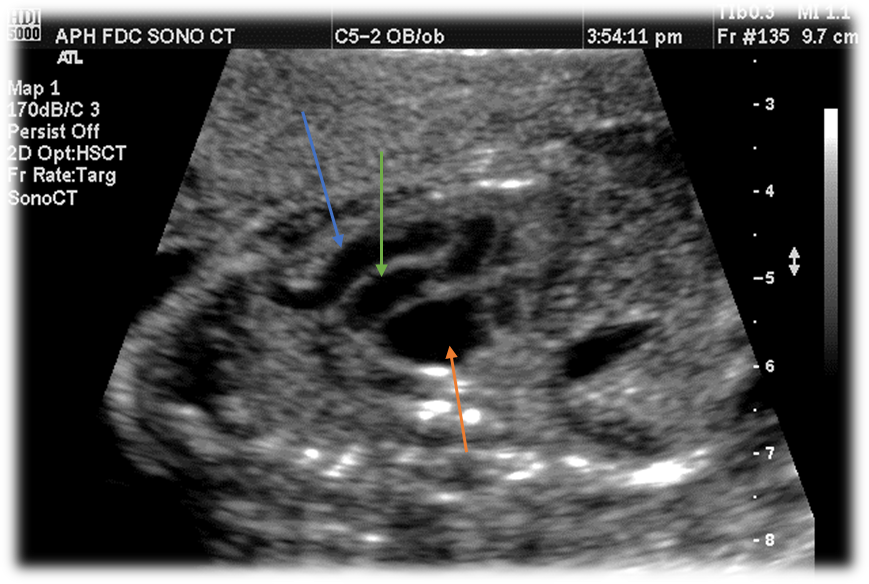

Label this image.

Blue - Aorta

Green - Pulmonary Artery

Orange - Left atrium

With Transposition of Great Vessels, vessels do NOT ________, they run ______ to each other.

Crisscross

Parallel